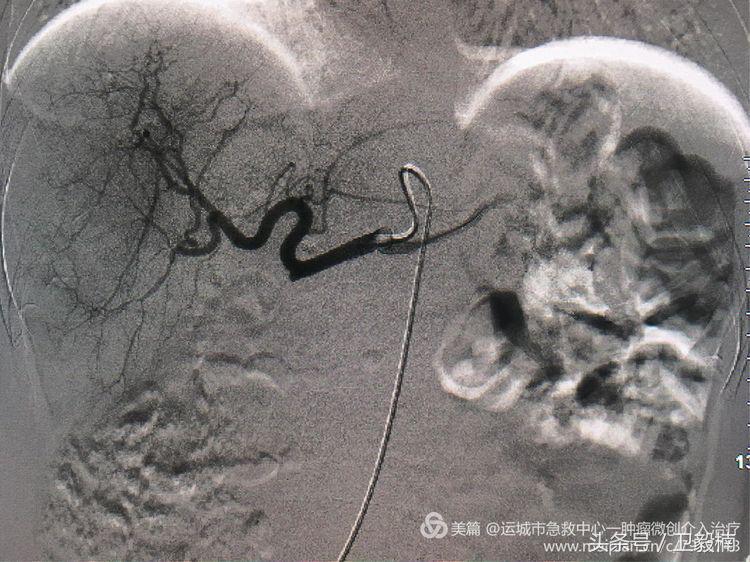

肝巨大转移瘤 肿瘤微创介入治疗中心开展肝动脉化疗药物灌注术,术后患者腹部疼痛明显减轻,

为解决腹痛及控制转移瘤来我院行介入治疗。

经过肿瘤的供血动脉给肿瘤灌注高浓度的化疗药,杀灭肿瘤细胞,再给注入栓塞剂,让肿瘤缺血坏死。达到饿死肿瘤的目的